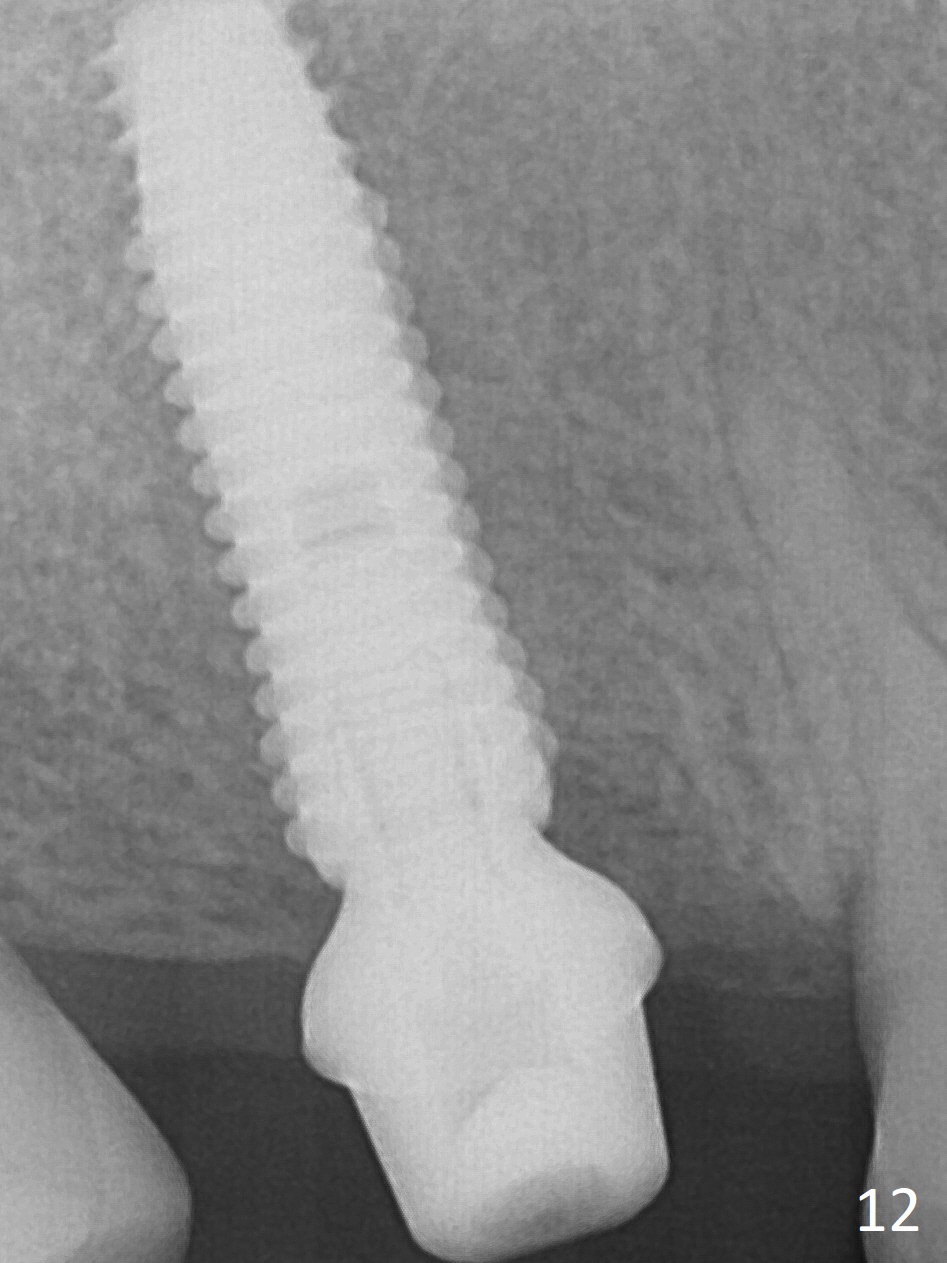

The palatal cusp of the affected 2nd premolar is apparently rotated distal (Fig.1). It is more obvious for the socket (Fig.2): the palatal (P) portion of the socket is more distal than the buccal (B) one. When the gauze is removed (Fig.3), Lindamann bur is used to remove the disto(D)palatal bone of the socket (data not shown), followed by starter drill in the DP wall obliquely (Fig.3'). Once the drill enters the bone for 1-2 mm, the bur is straightened and pushed slightly distal (Fig.3''). Fig.4 shows a parallel pin distal (overcorrect) to the original socket (Fig.4 red dashed line). Sequential osteotomy is conducted until 3.8x13 mm drill for 18 mm (Fig.5): note the 2 steps of the osteotomy (red lines). Since the apical portion of the osteotomy is larger than the drill, a larger implant than expected (5x16 mm) is placed. The implant ends up in the middle of the edentulous area (due to the stepped osteotomy; Fig.6-9; >60 Ncm). Vera allograft is placed (Fig.7-9 *) prior to and after placement of a 6.5x4(3) mm abutment (Fig.8-10). The remaining socket opening is sealed with a piece of Collagen plug (Fig.10 *). The socket is then closed by an immediate provisional (Fig.11 P). The abutment is retightened 2 months postop (Fig.12,13). The crown is cemented 4.5 months postop. Panoramic X-ray and CT are taken nearly 7 months post cementation (Fig.14,15) when the patient is ready for #30 implant guide preparation.